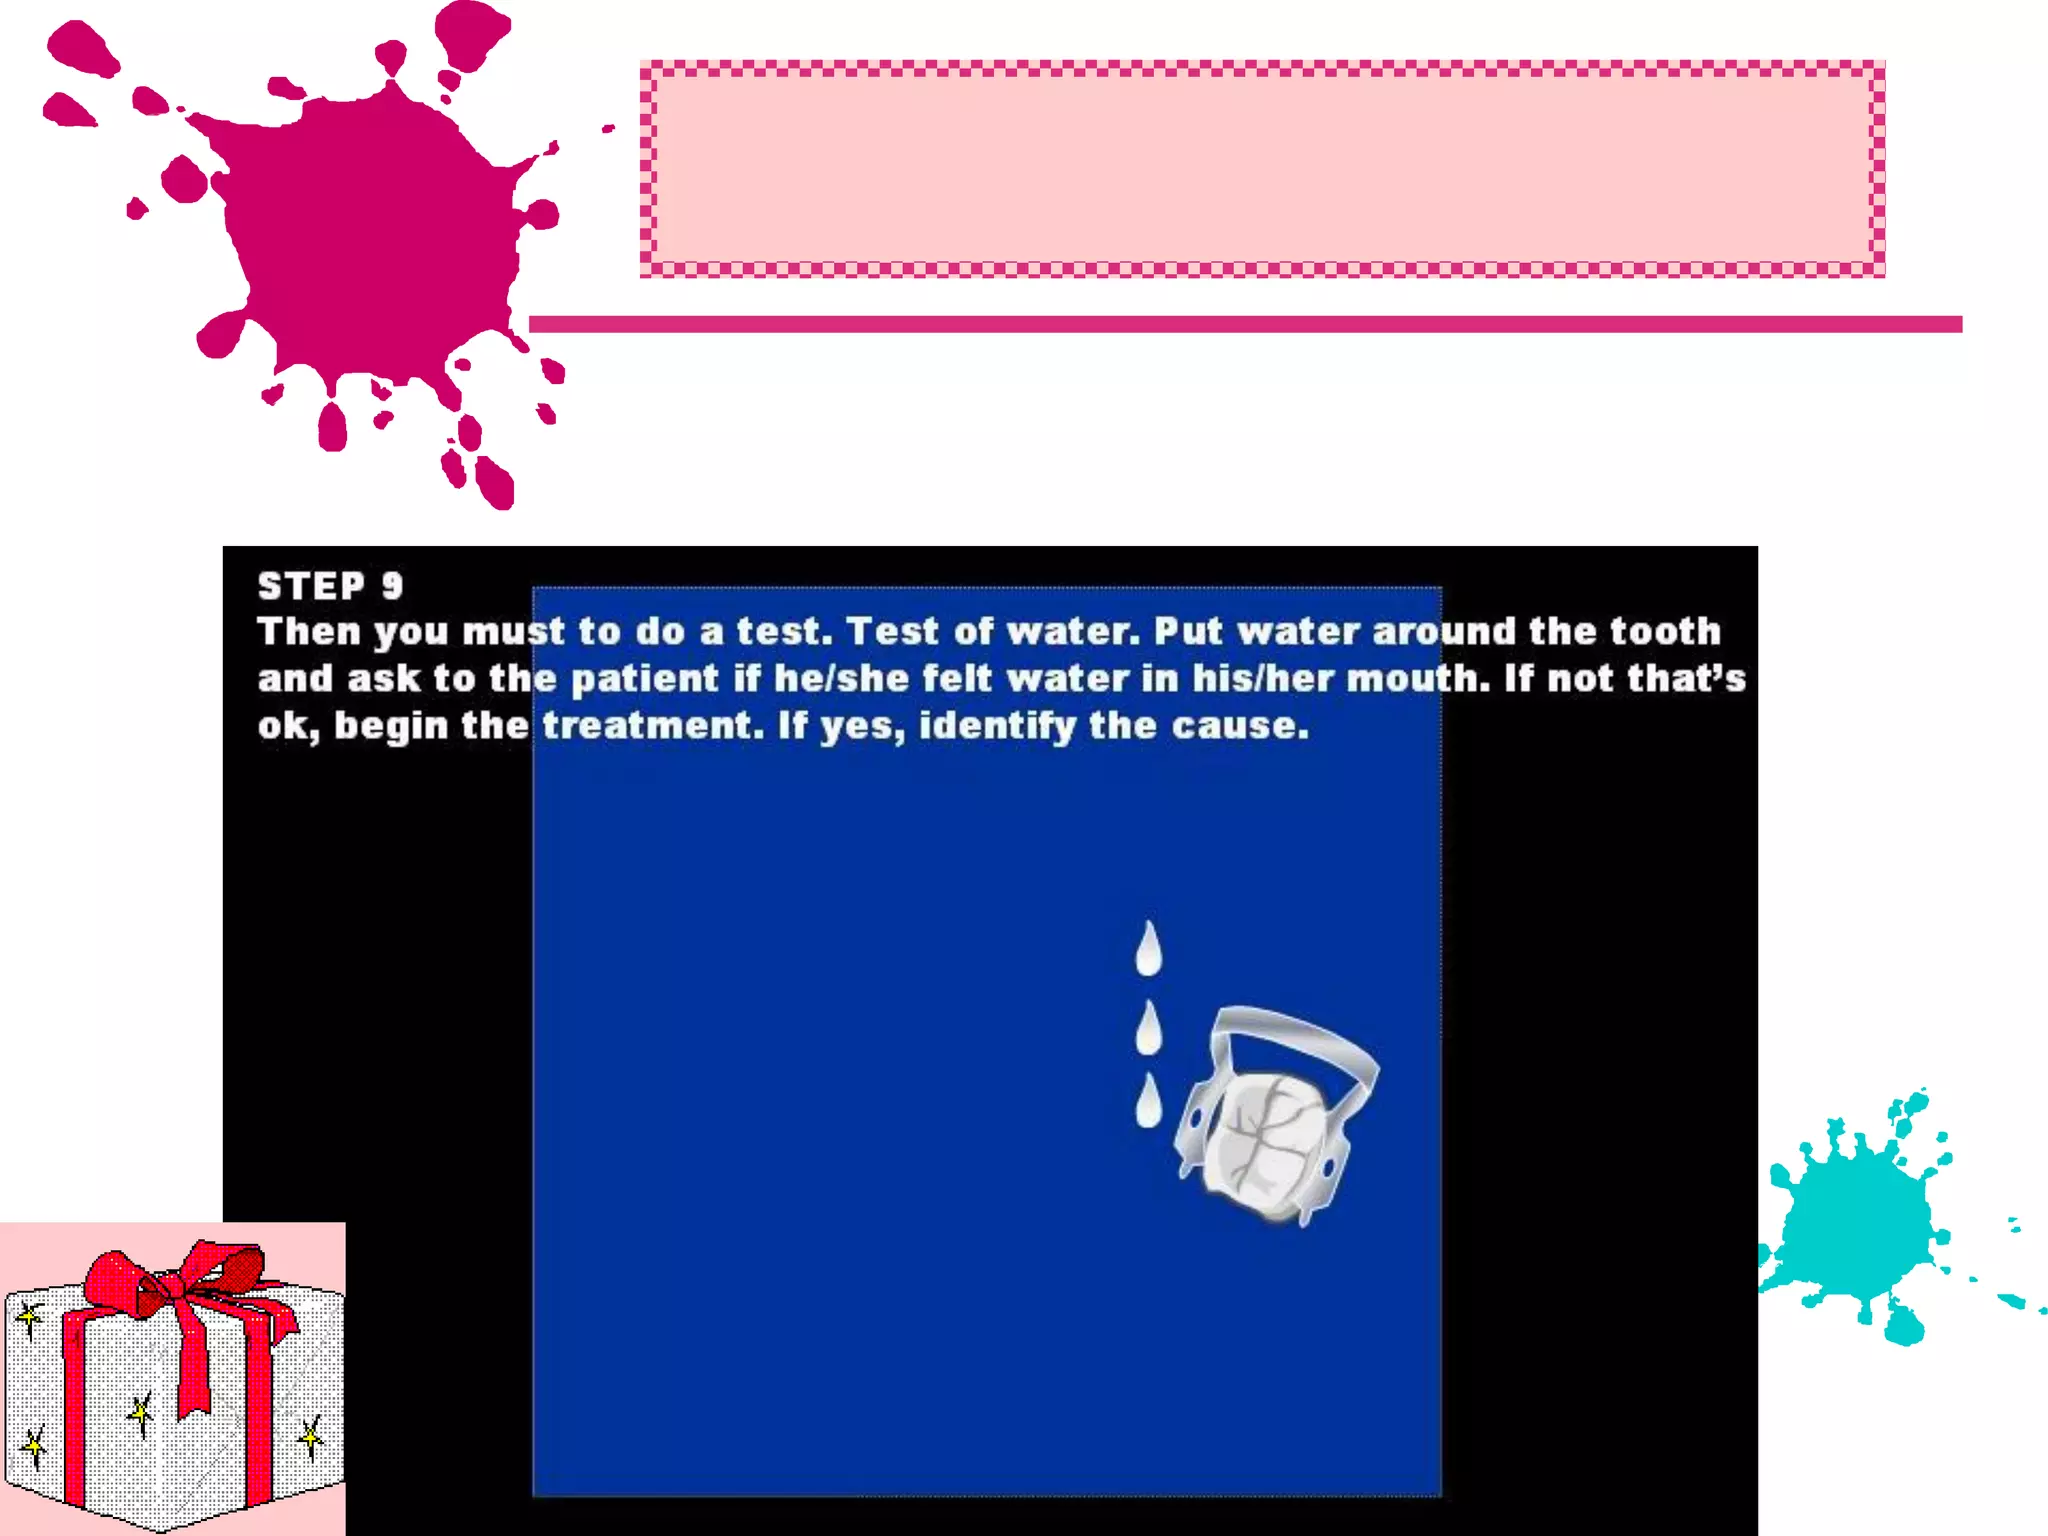

This document discusses the materials and components used for rubber dam isolation in dentistry. It describes the different types of rubber dam materials including color options and napkins to absorb moisture. It also outlines the tools needed such as punches to make holes, templates and stamps to guide hole placement, clamps to secure the dam, and other accessories like wedges and lubricant. Finally, it provides guidance on punching holes for different types of teeth and properly placing clamps in the rubber dam.